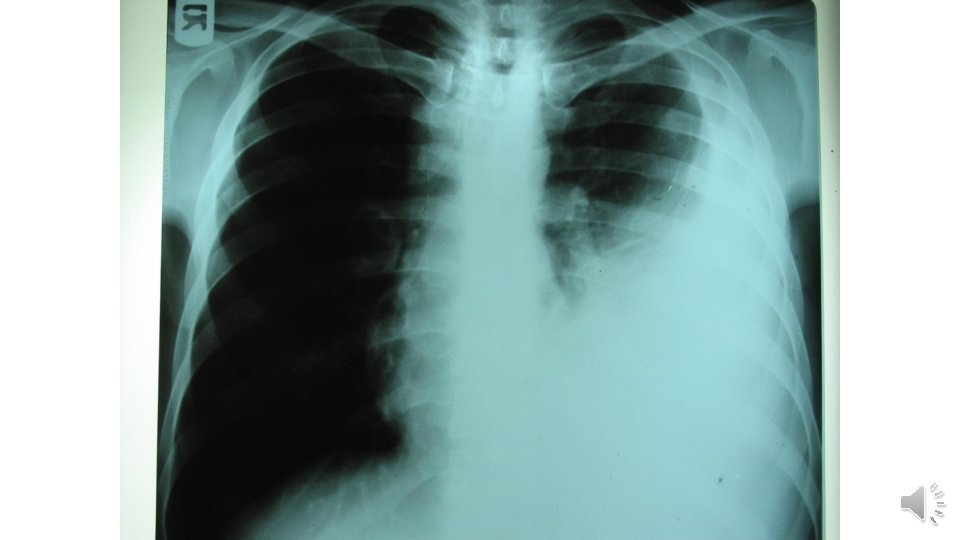

CXR

What your first diagnostic approach